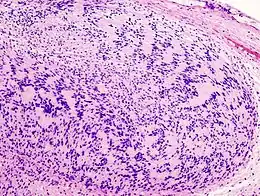

Illustrations

Neurinome subcutané_Antoni_B.jpg)

_Antoni_B.jpg)